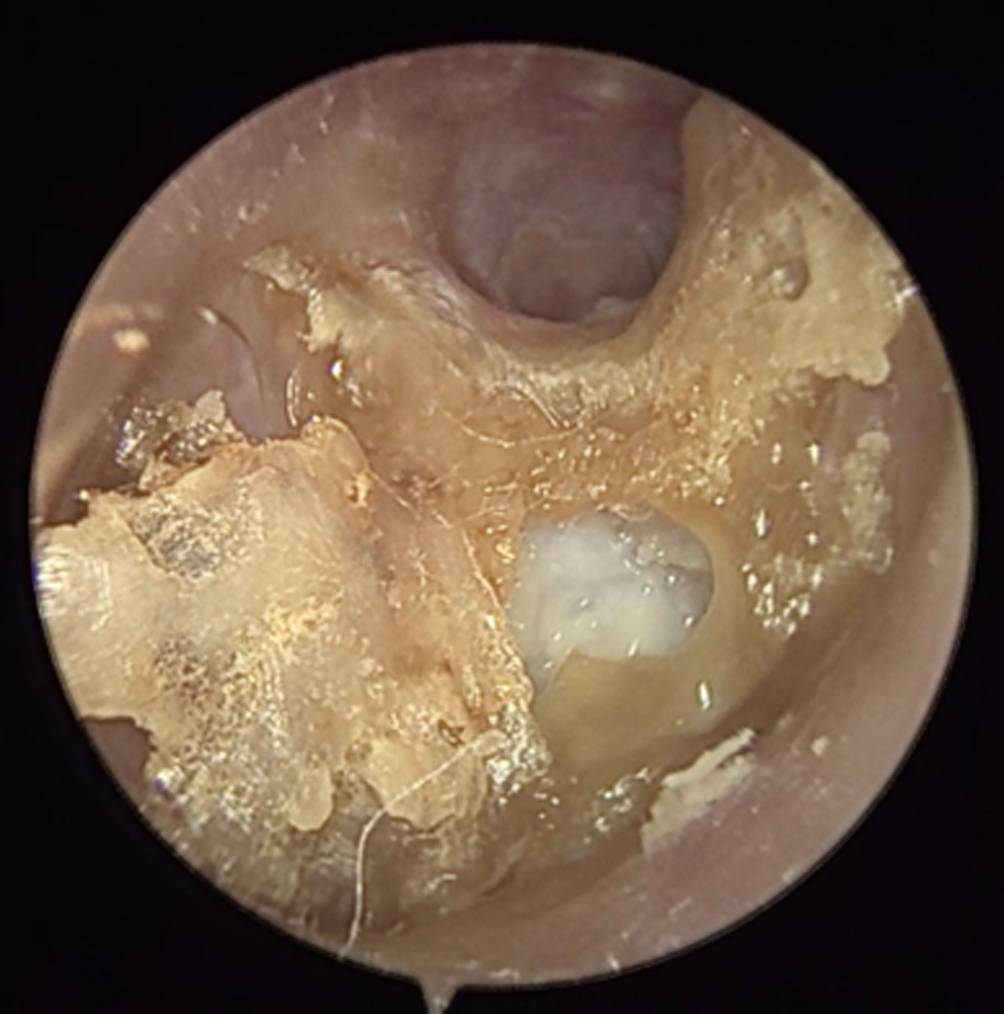

Abb. 5

Bild eines Gehörgangscholesteatoms mit Stufenbildung am Gehörgangsboden, freiliegendem Knochen (weißlich) und aufgelagerten Keratinkrusten (gelb)

Die seltene Differenzialdiagnose des Gehörgangskarzinoms sollte bei jedem Fall einer OEN mitbedacht werden und bei potenziellem Verdacht eine Biopsie zur histopathologischen Aufarbeitung entnommen werden (Abb. 4; [11]). Eine weitere Differenzialdiagnose stellt das Gehörgangscholesteatom dar (Abb. 5). Hier kommt es typischerweise zu einer von festen Krusten bedeckten Aushöhlung im Bereich des Gehörgangsbodens mit freiliegendem Knochen. Eine sichere Abgrenzung zur OEN erfordert bildgebende Verfahren, anhand derer eine Ausbreitung der Entzündung über die Grenzen des Gehörgangs hinaus ausgeschlossen werden kann.